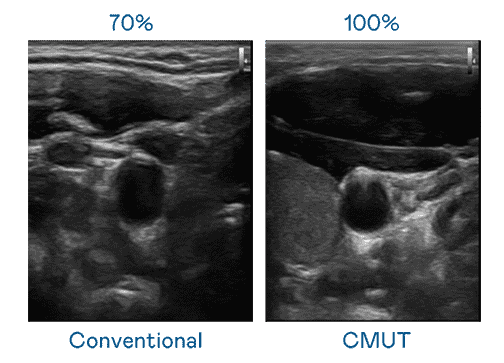

CMUT 技术是一种用电容式微机电元件来产生超音波讯号的技术。。与传统 PZT 压电式技术相比,,,,CMUT 频宽增加 30%,,更宽频的超音波讯号让影像解析度大幅提升,,是实现高影像品质医疗超音波扫描、、促进精准医疗发展的关键技术。。

大频宽带来超清晰影像

超音波影像的解析度高低,,首先取决于探头能发出的讯号频宽。。。。至成国际 CMUT 可提供高清晰的超音波讯号,,,,提供高频宽、、高灵敏度、、影像纹理细节更高的超音波影像,,,协助医护人员缩短影像判读时间及利用精准的医疗影像进行诊断。。。